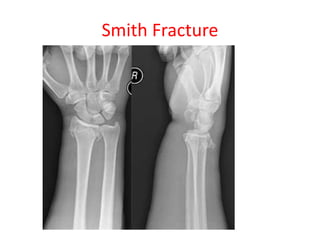

Smith’s fracture- Reverse of Colle’s fracture

• If distal fragments gets displaced anteriorly

Smith Fracture

Colle’s fracture- • Radiusgets fractured about 2 cm above its lower end due to fall on outstretched hand Smith’s fracture- Reverse of Colle’s fracture • If distal fragments gets displaced anteriorly